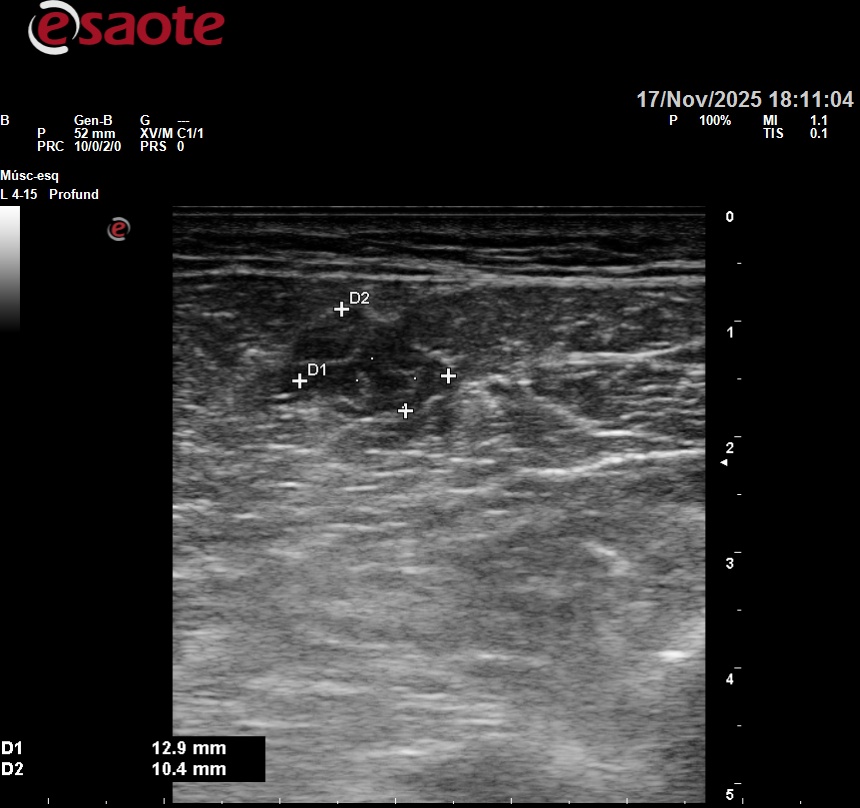

Se realiza una ecografía en el propio PAC, que evidencia una alteración estructural compatible con rotura fibrilar.

Hallazgos ecográficos

Pérdida de continuidad de fibras musculares en gemelo interno, con área hipoecoica sugestiva de hematoma intramuscular.

La exploración ecográfica permite descartar trombosis venosa profunda y lesiones tendinosas asociadas.